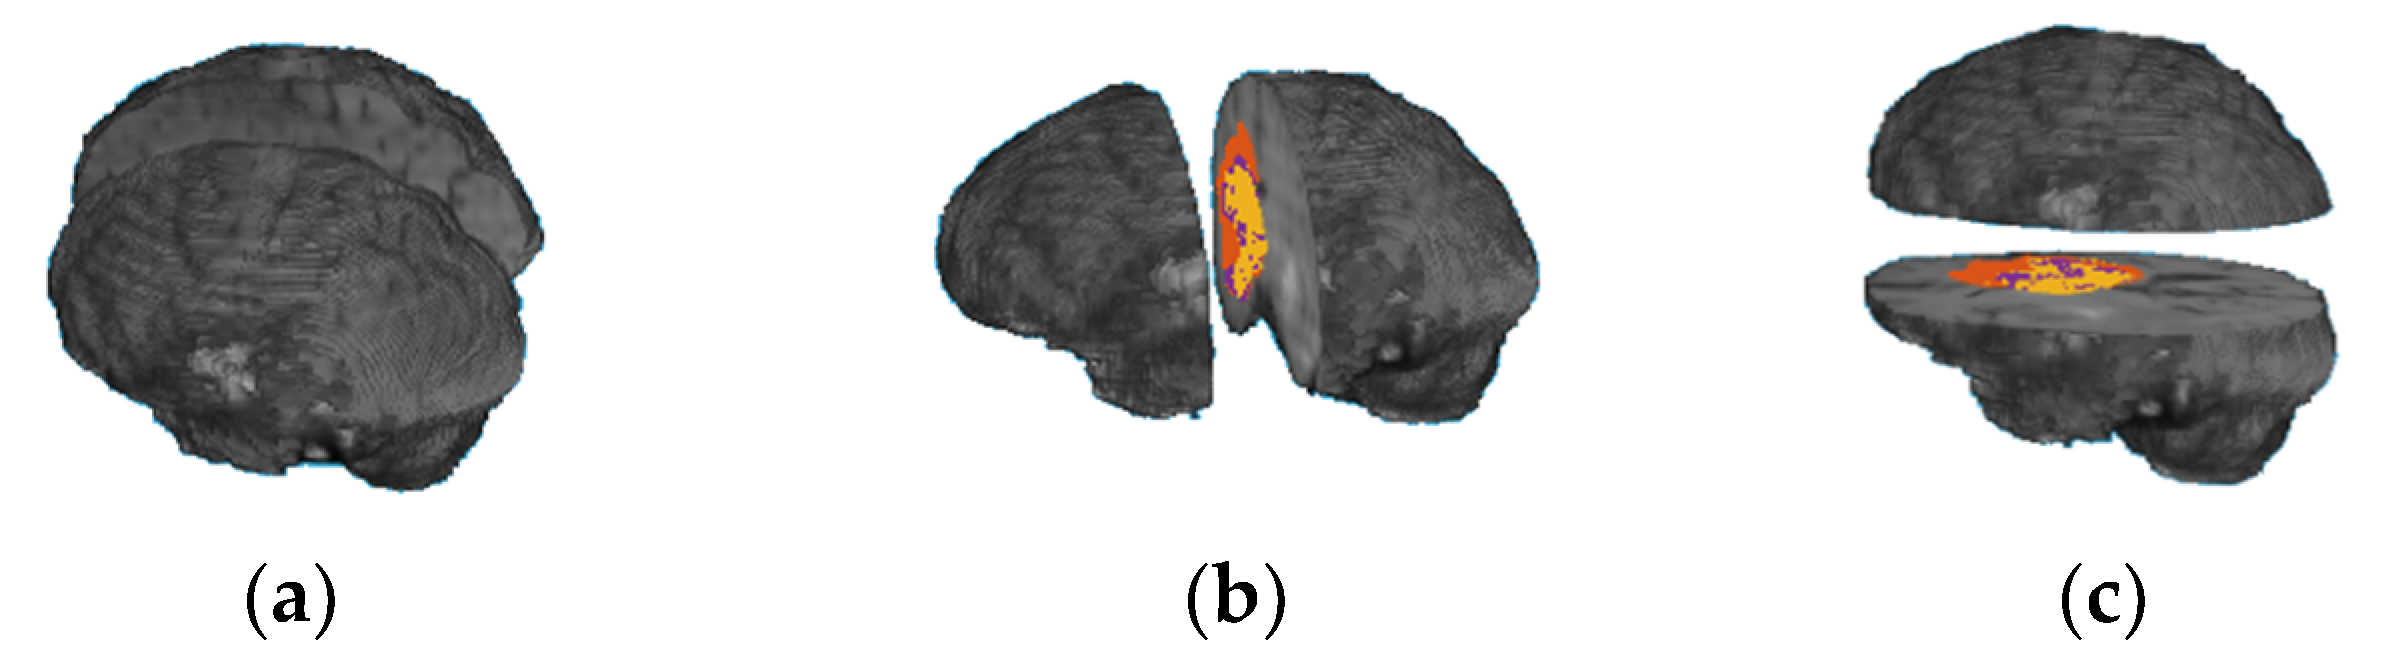

A human’s brain and body are divided into two sides, right and left, using the mid-sagittal plane. Each body part is controlled by the opposite part of the brain; for example, the left part of the brain controls the right side of a human body and vice versa. Each brain part contains four main functional regions (lobes): frontal lobe, occipital lobe, parietal lobe, and temporal lobe. In addition, there are other regions of the brain, called the cerebellum and the brain stem. Each of these functional regions is associated with different functions. The main idea of this paper was to develop an OST based on ML methods and volumes of a whole tumor region, as well as the tumor subregions extracted from each brain functionality region (lobe). However, we did not find a software program that could automatically identify each brain functionality region accurately in MRI scans. Therefore, we propose a novel alternative method based on dividing a brain volume into two sub-volumes, using brain sectional planes to calculate volumetric features in each brain sub-volume. Three different approaches are used to divide a brain volume in an MRI scan into two sub-volumes using one of the three brain functional planes, as shown in Figure 5. The first approach is based on using the mid-sagittal sectional plane to divide the brain volume in an MRI image into left and right volumes; the second approach is based on using mid-coronal sectional plane to divide the brain volume into anterior and posterior volumes; and the third approach is based on using the mid-horizontal plane to divide the brain volume into superior and inferior volumes. Twelve volumetric features are calculated from each approach. Five features are extracted from each brain sub-volume, representing the volume of the brain region (Vb), the volume of the whole tumor (Vwt), the volume of the gadolinium (GD)-enhanced tumor, the volume of the NCR/NET tumor, and the volume of the edema. Another two features are extracted from the whole brain volume, representing the volume of the whole brain region and the volume of the whole tumor region. Table A1, Table A2, Table A3 list the 12 features extracted from the mid-sagittal, the mid-coronal, and the mid-horizontal approaches, respectively. The order of the features based on each brain volume is used to describe the location information. All the MRI scans were well normalized, processed, and resampled by the BraTS challenge, and the segmentation labels are provided for this well-processed data. Thus, the number of voxels in any brain tumor subregion represents the volume of that region. To calculate the volume of the whole brain in an MRI scan, the OTSU thresholding method is applied to extract the brain region in an MRI scan, and then the number of voxels for the extracted region is calculated.

Figure 5. Two brain sub-volumes using the three section plans: (a) mid-sagittal; (b) mid-coronal; (c) mid-horizontal.